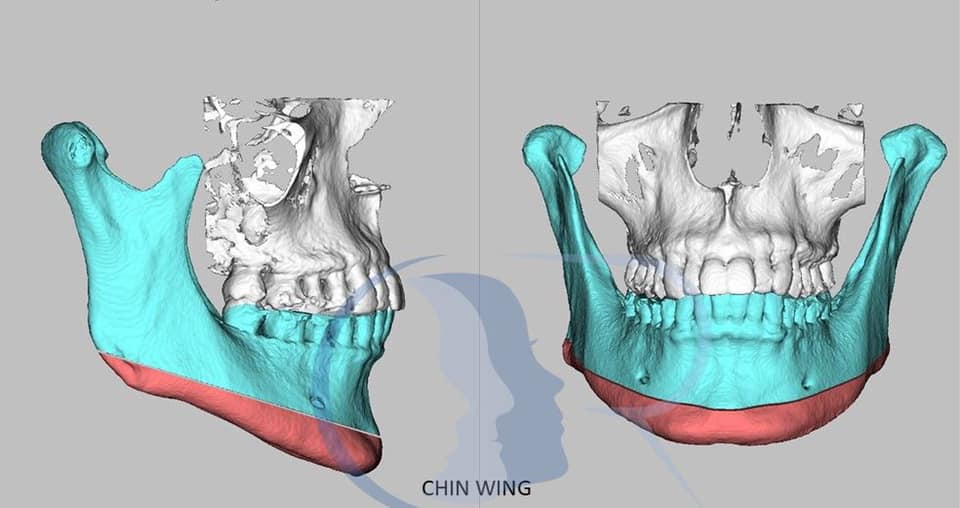

chin

chin is deviated a few mm sideways, and upturned in the side profile. would it be easier to just have the entire thing shaved off and augmented instead of doing genio? I'd get more freedom in my design and I think it's be a faster recovery.

jaw

if i do a chin implant, should I go ahead and design the implant to augment the entire mandible? fix the angle a bit and add some flare at the ends?

chin

chin is deviated a few mm sideways, and upturned in the side profile. would it be easier to just have the entire thing shaved off and augmented instead of doing genio? I'd get more freedom in my design and I think it's be a faster recovery.

jaw

if i do a chin implant, should I go ahead and design the implant to augment the entire mandible? fix the angle a bit and add some flare at the ends?